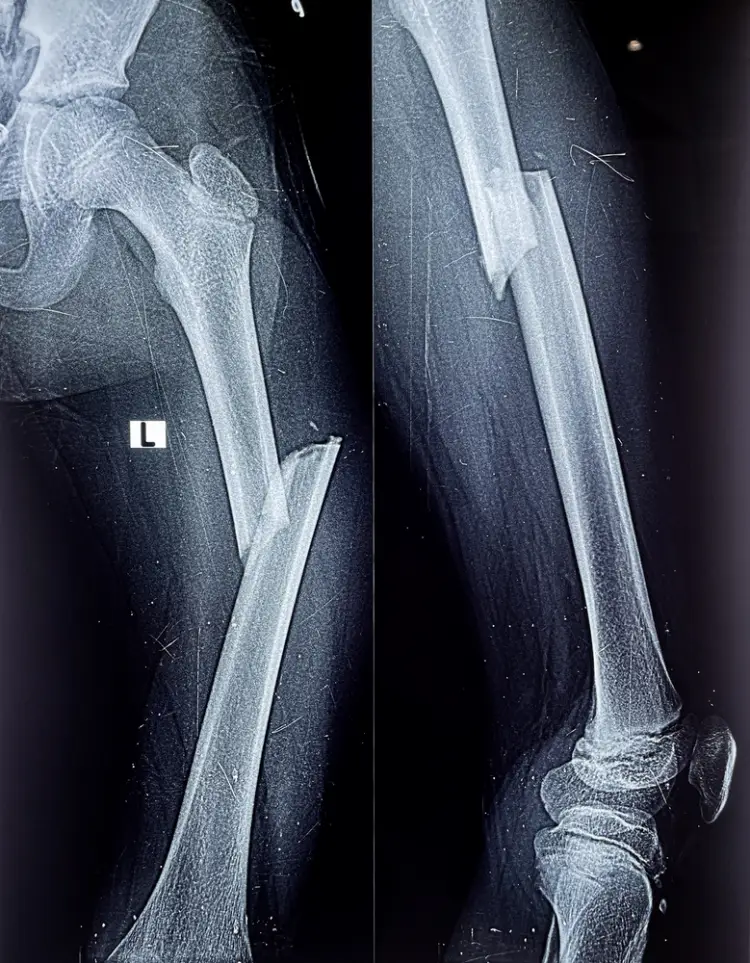

تعد عملية مسمار نخاعي في الفخذ إجراءً جراحيًا يهدف إلى تثبيت العظام المكسورة، حيث يمكن تركيب المسمار النخاعي في عظمة القصبة أو الفخذ أو العضد حسب موقع الكسر.

يساهم هذا الإجراء في دعم العظام وتعزيز سرعة التعافي، مما يسمح للمريض بالتحرك والمشي مبكرًا مقارنةً بعملية تثبيت العظام باستخدام الشرائح والمسامير التقليدية، التي تتطلب فترة انتظار أطول لالتئام العظام.

تتم العملية عن طريق إدخال قضيب معدني داخل عظمة الفخذ لتثبيتها بشكل قوي ومستقر. يمكن وضع هذا المسمار النخاعي داخل قناة عظم الفخذ من جهة الورك أو الركبة، مع تثبيت البراغي فوق أو تحت منطقة الكسر لضمان ثبات العظم أثناء فترة الشفاء، وتعرف هذه العملية باسم التسمير النخاعي و من المضاعفات الشائعة التي قد تحدث بعد العملية هي الالتهابات، والتي يجب التعامل معها بسرعة عبر: